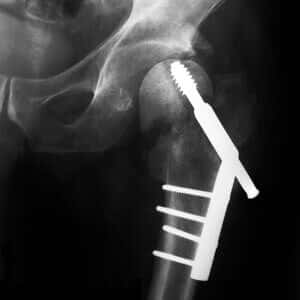

A. The hazards of long-term use of PPIs such as esomeprazole (Nexium) , lansoprazole (Prevacid), omeprazole (Prilosec) , pantoprazole (Protonix) and rabeprazole (Aciphex) have gradually become clearer. Data from nearly 80,000 women in the Nurses’ Health Study show that women who took PPIs were 30 to 35 percent more likely to fracture a hip during eight years of follow-up (BMJ, online, Jan. 31, 2012).

This can be devastating, particularly for older people. As one reader reported, “My mother took a PPI and then had a hip fracture. She died 19 days later.”